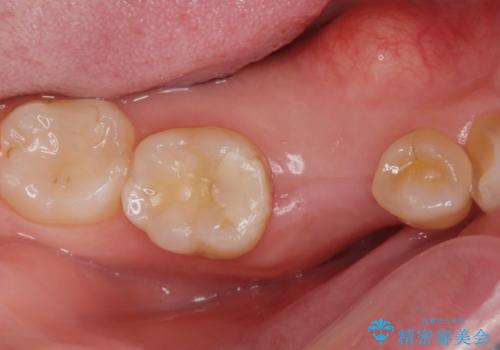

古い樹脂の詰め物を取り除いたところ、歯の神経と非常に近い状態でした。

万一神経と交通した場合に備え、唾液が入らないようにゴムのシートで防湿(ラバーダム防湿)を行い虫歯除去を行いました。

幸い神経とは交通せず、処置後の神経症状もありませんでした。

ご希望に沿って、ゴールドインレーにて治療を行いました。